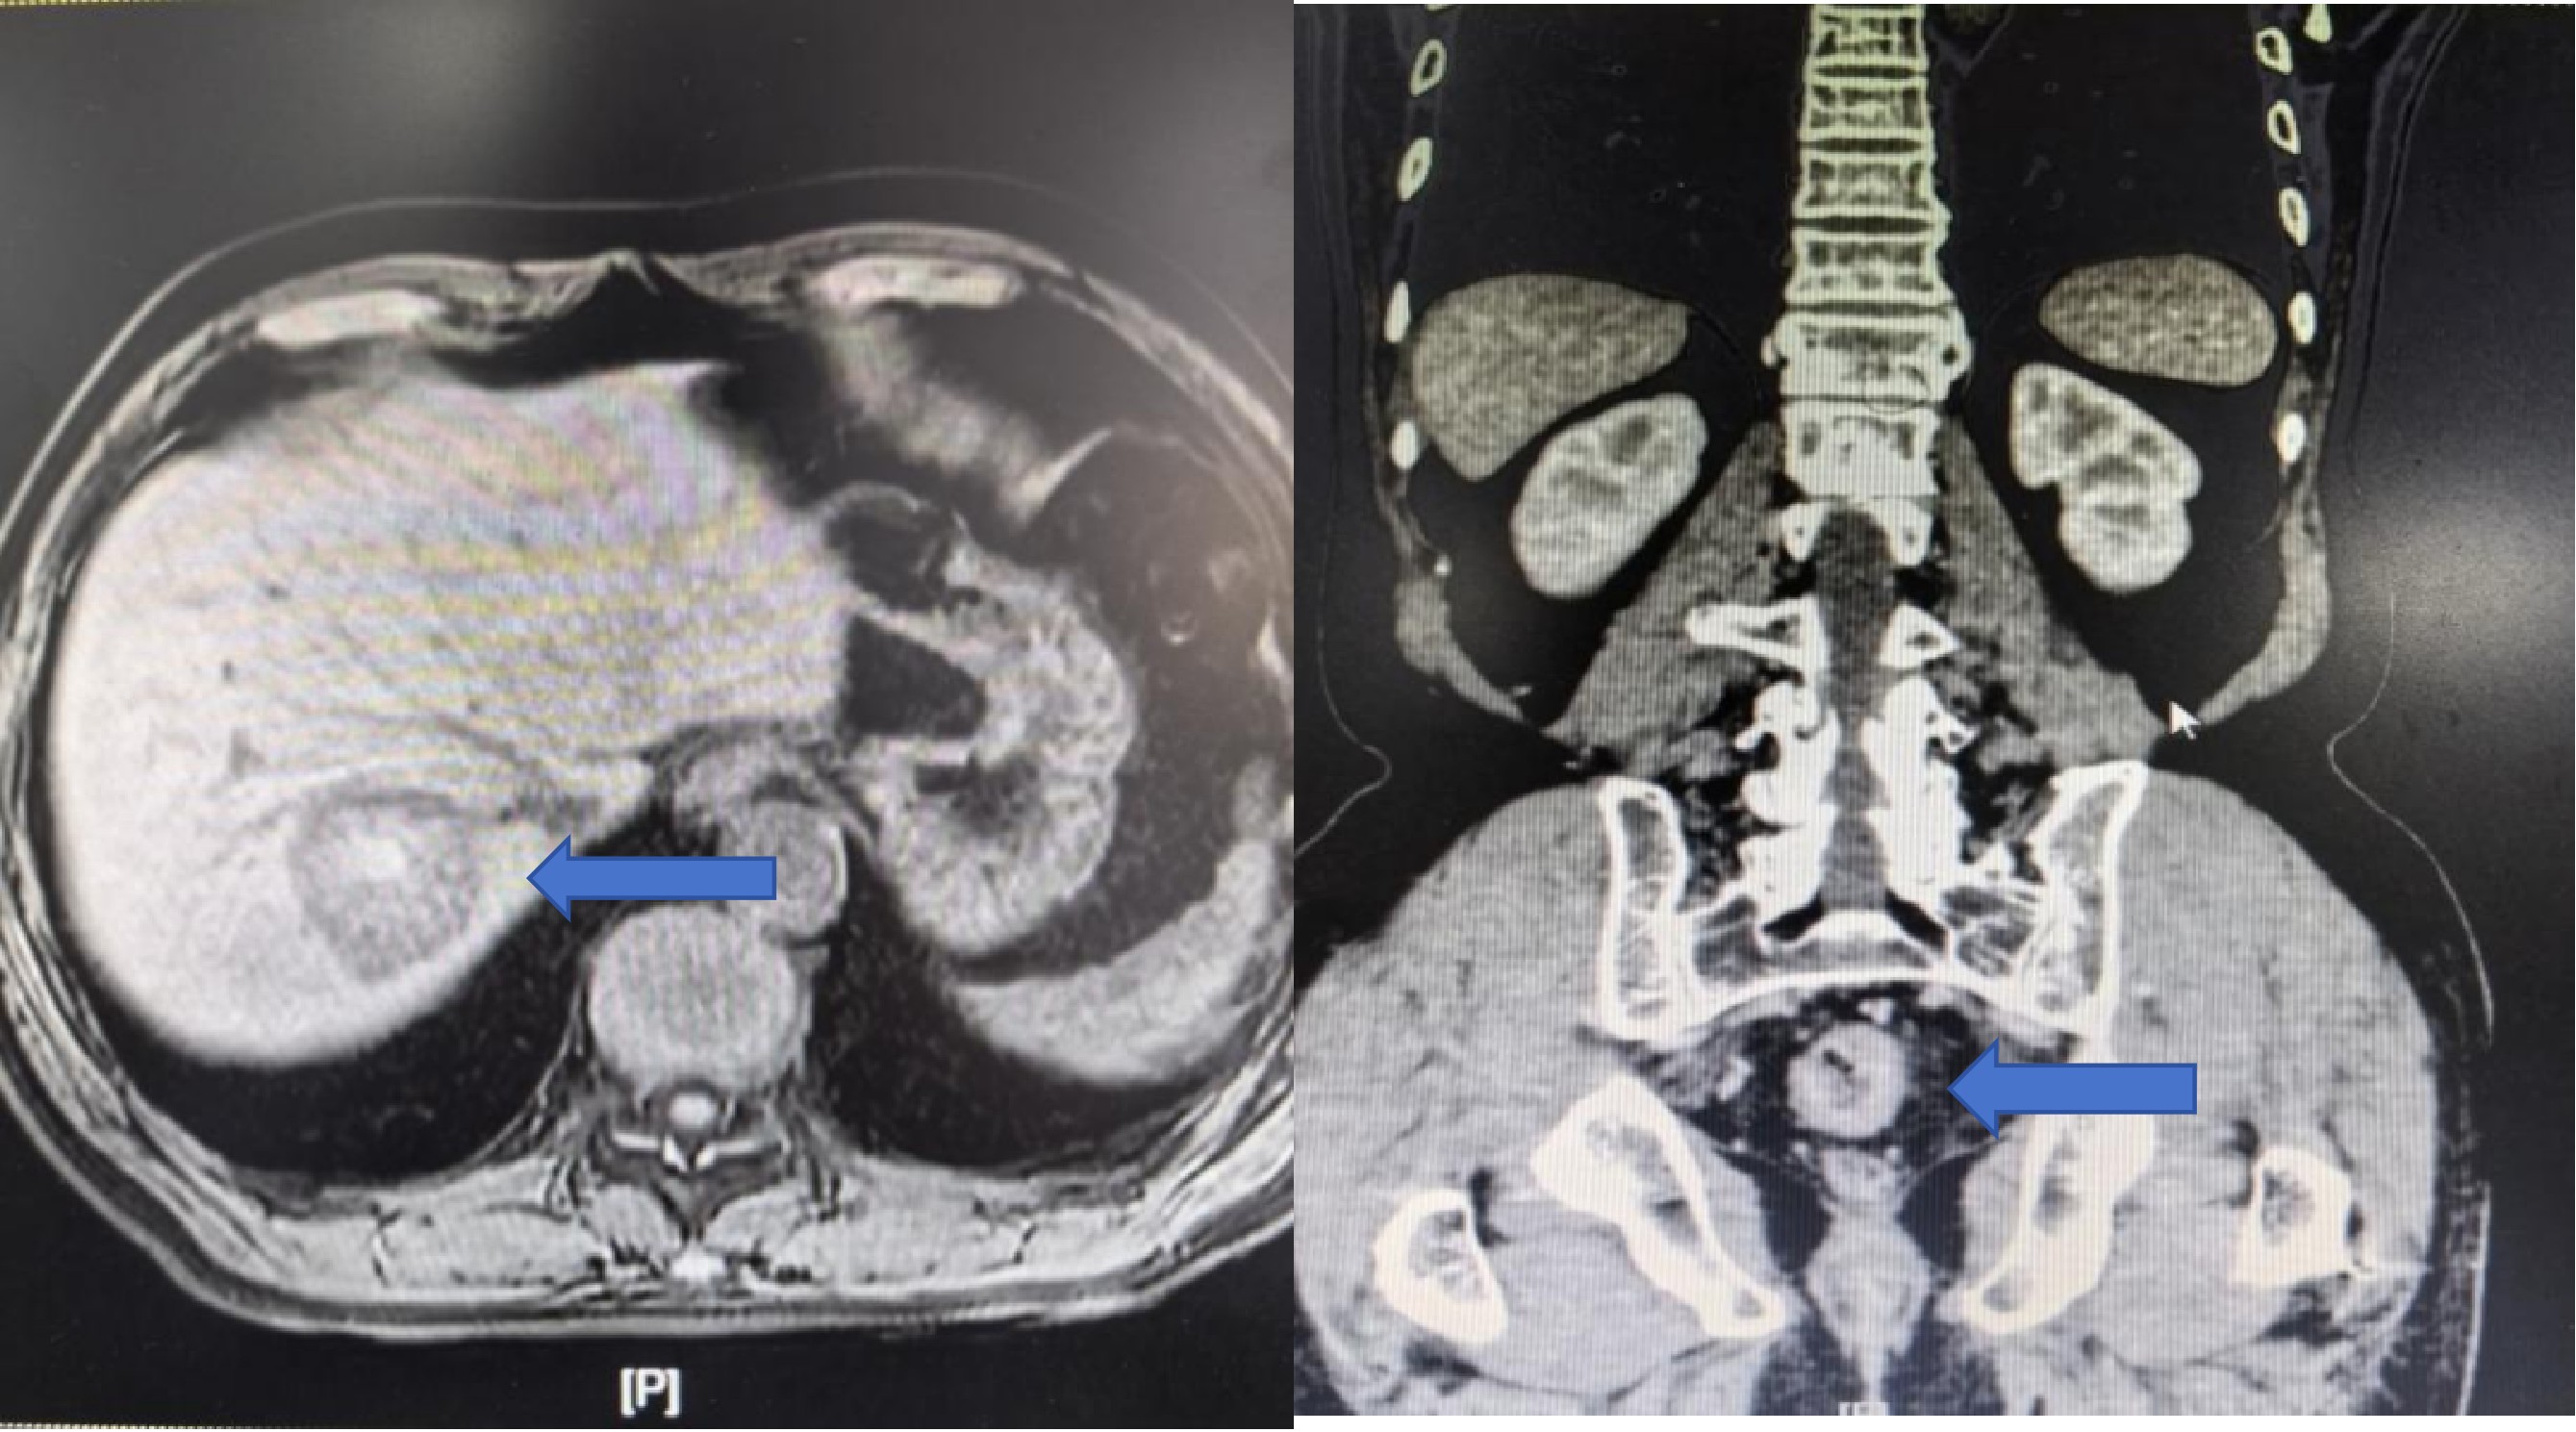

入院后,详尽的术前检查揭示了更为复杂的病情:腹部CT提示肝右叶存在异常高密度灶,高度怀疑为转移瘤并伴出血。肝脏MRI进一步明确了诊断:肝右后叶上段占位,考虑转移瘤并出血等。术前诊断清晰——直肠腺癌合并肝转移。面对这一直肠腺癌合并肝转移的复杂病例,是同时针对同期切除原发病灶与转移灶,还是先实施辅助治疗这一关键诊疗决策,朱利勇教授团队第一时间联合肝胆外科、肿瘤科、麻醉科、临床营养科等多学科专家开展MDT会诊。经过充分讨论与全面评估,专家团队一致认为,同期切除直肠原发病灶和肝脏转移病灶是当前对患者最有利的治疗策略,术后将根据病理结果辅以化疗等综合治疗。